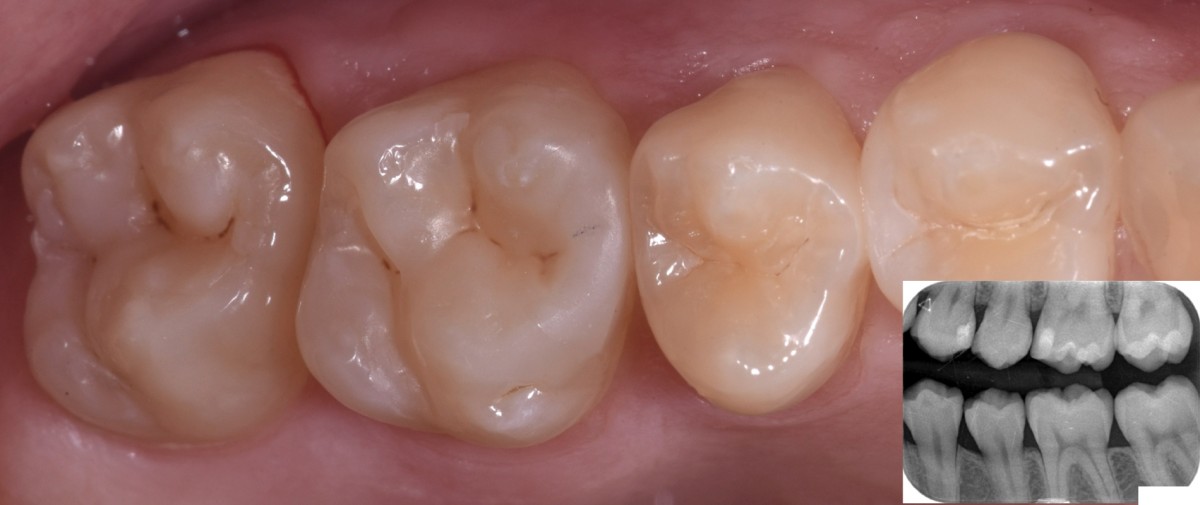

A 19-year-old female patient came to my attention reporting sensibility related to cold on the 2nd quadrant. The general medical history revealed nothing relevant. Clinical and rx bitwewing examination revealed primary interproximal decay of 2.6 mesial, with a possible involvement of 2.5 distal and an occlusal decay of 2.7. Vitality test was carried out and confirmed that all elements were vital. According to the young age of the patient and the good quantity of sound tissue structure, a minimally invasive approach with direct restorations was proposed.

Oral hygiene motivation was carried out, alongside with proper periodontal treatment (scaling, polishing) before taking initial photo and rx bitewing of the quadrant (Fig.1).